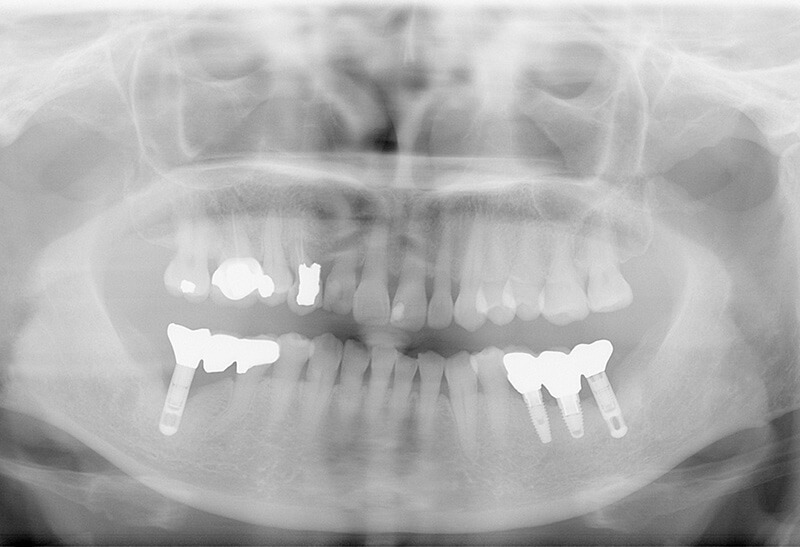

拯救他院植牙案例